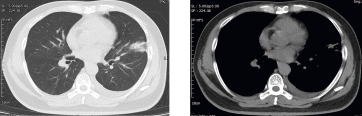

病例概要:患者,男性,50岁,主因“发现左肺上叶占位性病变2月余。”来诊。患者自诉2月前体检胸部CT,发现左肺上叶舌段实性占位,大小约2.5*2.3cm,与胸膜相连,可见分叶、毛刺,恶性可能性大,有咳嗽、咳痰,白痰为主,偶有黄痰,无痰中带血等异常,未采取治疗,定期复查。2周前再次复查胸部ct:左肺上叶占位性病变较前增大,侵犯下叶背段,大小约4.1*3.1cm,考虑肺癌可能。胸外科副主任医师胡晓丹在充分了解患者病情及影像检查后,指示病灶为实性结节且肿物增长过快,需完善全身检查明确有无肿瘤转移可能,后迅速完善全身PET-CT,发现左肺高代谢肿物位于左肺舌段及左下肺内前基底段,病变跨越斜裂胸膜(大小4.6*4.4,SUVmax9.1),恶性可能性大;纵隔、左肺门、右侧内乳区淋巴结转移瘤可能(大者短径1.6cm,SUVmax4.7)。考虑患者淋巴结转移瘤可能性大,需尽快明确病变淋巴结性质,给予经支气管超声内镜纵隔淋巴结穿刺活检术(EBUS-TBNA),胡晓丹会同胸外科医师赵洋乐顺利穿刺4R、4L区、7区、10L淋巴结,术后病理均未见肿瘤细胞,初步考虑淋巴结肿大为良性病变。但为明确肺部占位是否为恶性肿瘤,还需行CT引导下经皮肺病损穿刺活检术明确病变性质,术中操作顺利,无气胸、咯血等异常;术后穿刺病理:(左肺上叶结节)肺脓肿。最终诊断:肺脓肿,在给予2周规范消炎、化痰等治疗后,再次复查胸部CT,病灶大小较前明显缩小(约2.7*3.3cm),实性成分较前明显减少,最终避免了全麻手术切除,顺利出院。

术后消炎后胸部CT-肺窗 纵膈窗